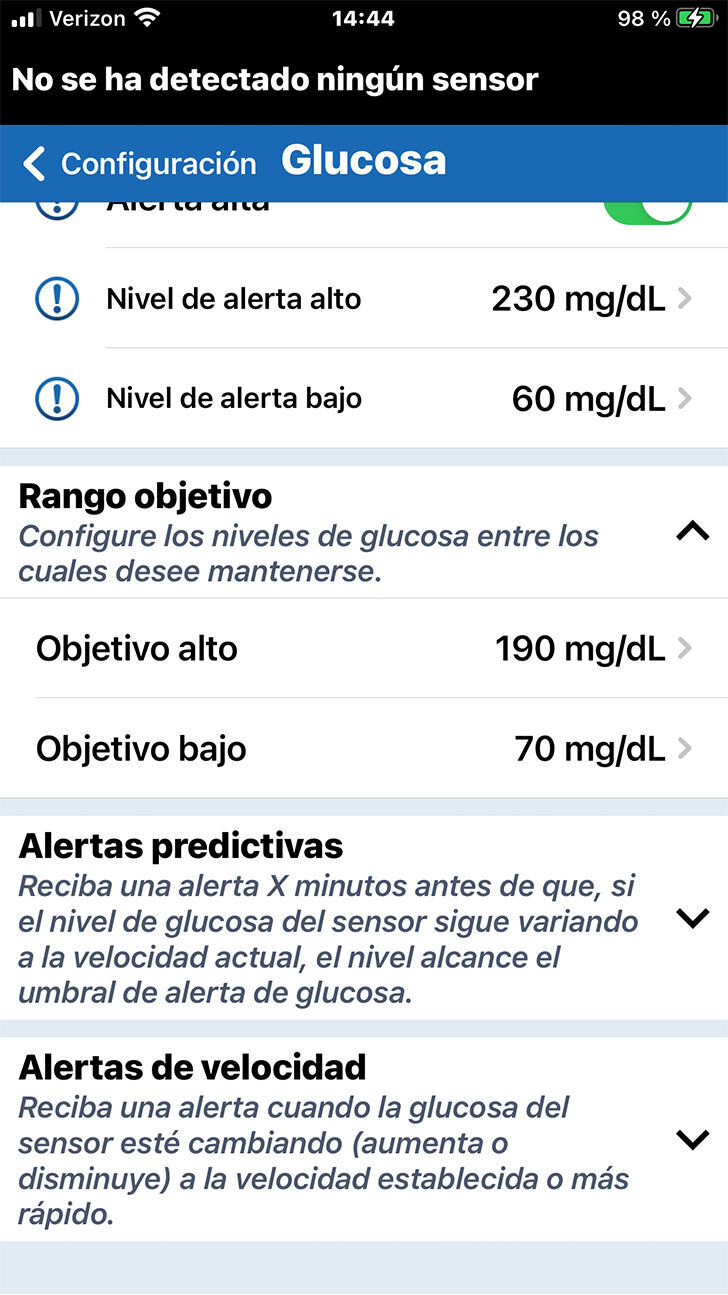

Debajo de Alertas de glucosa puede configurar su Intervalo objetivo de glucosa.

El intervalo objetivo de glucosa es la zona en la que tanto usted como el profesional de la salud deciden que deben estar sus niveles de glucosa la mayor parte del tiempo.

PERSONALICE LOS OBJETIVOS DE GLUCOSA

PERSONALICE LOS OBJETIVOS DE GLUCOSA

Nuevamente, solo tiene que tocar en el ajuste que le gustaría modificar, desplazarse hasta al valor deseado y, finalmente, tocar OK.

Debajo de Alertas de glucosa puede configurar su Intervalo objetivo de glucosa.

El intervalo objetivo de glucosa es la zona en la que tanto usted como el profesional de la salud deciden que deben estar sus niveles de glucosa la mayor parte del tiempo.

Tenga en cuenta que los niveles objetivo

de glucosa solo se pueden programar dentro de los niveles de alertas

de glucosa que ha definido.

PERSONALICE LOS OBJETIVOS DE GLUCOSA

Nuevamente, solo tiene que tocar en el ajuste que le gustaría modificar, desplazarse hasta al valor deseado y, finalmente, tocar OK.

Debajo de Alertas de glucosa puede configurar su Intervalo objetivo de glucosa.

El intervalo objetivo de glucosa es la zona en la que tanto usted como el profesional de la salud deciden que deben estar sus niveles de glucosa la mayor parte del tiempo.

En esta pantalla, también puede definir alertas predictivas y de velocidad de cambio.

Las alertas predictivas pueden

ser especialmente útiles para

los usuarios de la MCG.

No obstante, si es su primera vez con

la MCG, puede que lo mejor sea esperar para configurar estas alertas opcionales hasta que hable de estos ajustes con

su profesional de la salud.

Consulte la Guía del usuario para obtener más información.